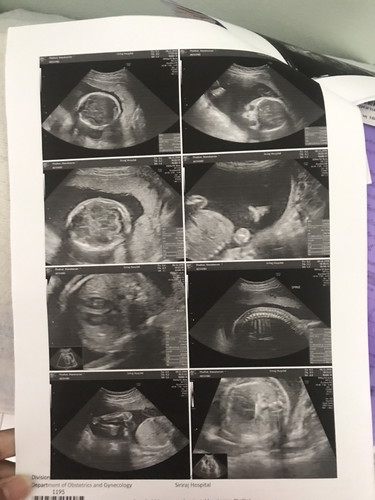

อยากรู้ว่าเป็นหญิงหรือชายหมอบอกหญิง90%แต่ไปๆมาๆไม่ค่อยแน่ใจแล้วค้า